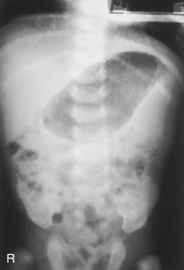

• Supine, legs extended, arms at sides

• Midsagittal plane aligned and centered to centerline

• Ensure no rotation (ASISs equal distance from tabletop)

• Center of IR to level of iliac crests, ensuring that upper margin of symphysis pubis is included on lower IR margin. (A large hypersthenic patient may require that the IR be placed crosswise with a second IR centered higher.)

• Arrow marker to include upside